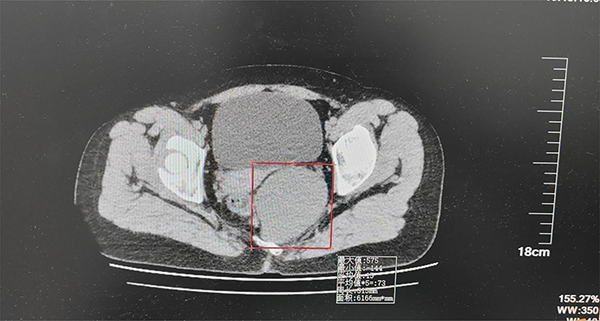

妇科微创肿瘤病房主任滕颖与医生吴爱弟仔细为武女士进行查体,考虑到患者未婚,便选择了肛诊方式,高度怀疑肿物源自腹膜后,随即安排全腹增强 CT,结果显示盆壁左后侧有大小约 9.8×7.7×6.1cm 的囊性肿物。

术中,滕颖主任精准施术,凭借丰富经验与精湛技巧,步步为营,带领妇科团队奋战3小时,成功完整剥除畸胎瘤,病理结果确诊为盆腔腹膜后囊性成熟性畸胎瘤。术后滕颖主任丝毫未放松,由于腹膜后手术盆腔引流时间较长,她多次亲查病房,耐心安抚武女士情绪,助力康复。术后第8天,武女士顺利出院。